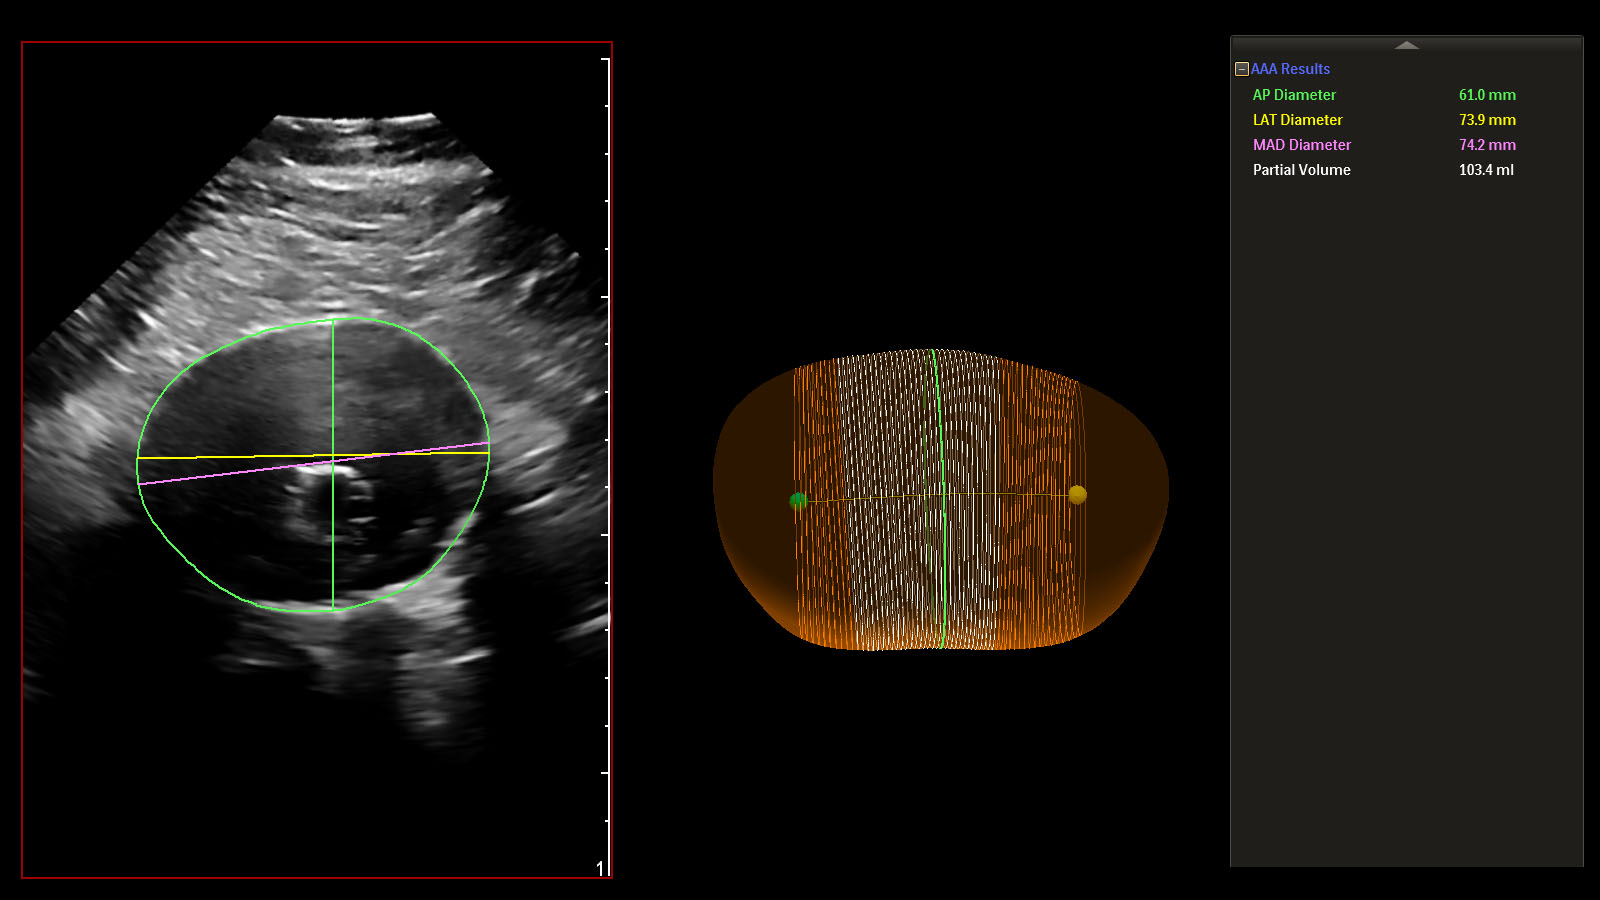

Amsterdam, the Netherlands, Jan. 27 (Korea Bizwire) – Royal Philips (NYSE: PHG, AEX: PHIA), a global leader in health technology, has introduced the Philips Abdominal Aortic Aneurysm (AAA) Model, providing physicians a more patient-friendly solution compared to the current standard of care for managing AAA patients. Based on 3D ultrasound, Philips AAA Model delivers clinicians accurate diagnostic information without exposing patients to high doses of radiation and nephrotoxic contrast agents.

An abdominal aortic aneurysm (AAA) is an aneurysm that forms in the lower part of the aorta. Typically, AAAs are identified incidentally during abdominal imaging exams but, in some cases, remain undetected until rupture. A ruptured AAA has an 80% mortality rate [1], emphasizing the importance of routine surveillance. Philips AAA Model integrates innovative software and leading Philips 3D ultrasound technologies into a single solution to help increase diagnostic confidence and an improved patient experience. The software automatically segments and quantifies the size of the aneurysm sac for surveillance of known native (untreated), and post-EVAR (treated) AAAs.

A recent clinical study showed that 3D ultrasound examination for native AAA surveillance has excellent inter-operator reproducibility, superior to that of 2D ultrasound, supporting the broader use of 3D ultrasound in standard AAA surveillance programs [2]. 3D ultrasound has been shown to estimate the diameter and volume of an AAA with acceptable reproducibility and an improved agreement (over 2D ultrasound) with CT [3]. Furthermore, 3D ultrasound has also been proven to correlate significantly better to 3D CT than 2D ultrasound for assessing the maximum diameter of the residual sac post-EVAR, with clinically acceptable reproducibility [4].